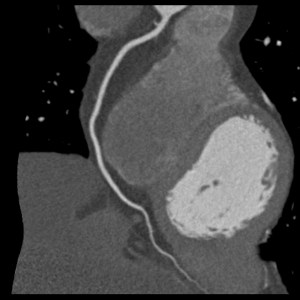

RCA

RCA-Stenose

Eine CT-Angiographie kann insbesondere sinnvoll sein bei Patienten ohne bekannte KHK mit unklarem Brustschmerz oder Atemnot, bei denen EKG-Untersuchungen, Echokardiographie und Bluttests keinen eindeutigen Hinweis auf eine Einengung der Herzkranzgefäße gezeigt haben. Die CT-A kann, auf der Basis unserer modernen CT-Technologie, die Herzkranzarterien hochaufgelöst und trotz schlagenden Herzens bewegungsfrei darstellen, so dass es uns Ärzten möglich ist, nicht nur Gefäßverschlüsse, sondern auch den Schweregrad einer Gefäßeinengung zu detektieren. Hieraus ergibt sich eine mögliche Aussage über die Notwendigkeit einer invasiven Herzkatheteruntersuchung bei einem Kardiologen zur weiteren Abklärung bzw. Behandlung des im CT erhobenen Befundes. Somit können durch die Herz-CT-Untersuchung unnötige invasive Herzkatheteruntersuchungen bei Patienten verringert werden.

Dieser Anwendungsbereich der Herz-CT ist bereits in einem gemeinsamen Konsensuspapier der Deutschen Gesellschaften für Kardiologie und für Radiologie als sinnvoll festgehalten worden. Darüber hinaus können mittels der CT-A des Herzens bei vorbehandelten Patienten nicht invasiv die Herzbypässe auf Durchgängigkeit kontrolliert werden. KHK-Patienten mit einliegenden Koronarstents können in Abhängigkeit von der Art und der Durchmesser der eingebrachten Stents ebenfalls mittels Herz-CT untersucht werden, wobei bei diesen Patienten Einschränkungen der Aussagekraft vor allem bei Stents kleiner 3,5 mm Durchmesser und bei alten Metallstents bestehen.

Insgesamt besteht eine Einschränkung der Aussagekraft der CT-A bei sehr stark verkalkten Herzkranzarterien. Daher machen wir in unserer Praxis vor der eigentlichen CT-Angiographie immer einen nativen CT-Scan für den Kalk-Nachweis, um Patienten mit einer ausgeprägten Konorasklerose herauszufiltern und ihnen einen unnötige Kontrastmittelgabe zu ersparen. Solche Patienten sollten im Umkehrschluss zur weiteren Abklärung einer Herzkatheteruntersuchung zugeführt werden.